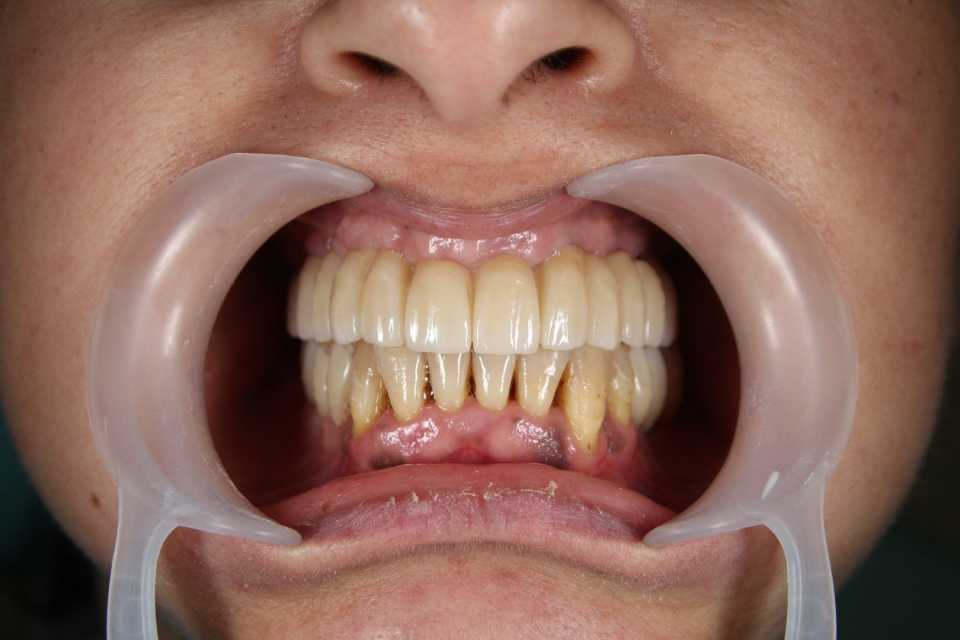

Împreună cu pacienta, am optat pentru un tratament complex, realizat într-o singură ședință. S-au efectuat extracțiile dinților parodontotici, chiuretajul pungilor parodontale și inserarea a 4 implanturi Mega-Gen AnyRidge la nivelul maxilarului. Cu ajutorul capelor multiunit, s-a reușit protezarea imediată, prin aplicarea unei lucrări provizorii din acrilat, la doar 24 de ore de la intervenție. După 2 luni, tratamentul a fost finalizat prin realizarea unei lucrări definitive, înșurubabile, din ceramică pe suport de zirconiu, cu 12 elemente.

La nivelul mandibulei, reabilitarea zonelor laterale premolar-molar s-a realizat prin inserarea a câte două implanturi pe fiecare parte, protezate după 2 luni cu două lucrări din ceramică pe suport de zirconiu, cimentate. Dintii restanți ai mandibulei au fost conservați după tratamentul parodontal și solidarizați printr-o contenție linguală.

Implanturile dentare oferă un suport pentru dinții artificiali, eliminând orice neplăceri provocate de aceștia. În plus, implanturile îmbunătățesc masticația și vorbirea. Acestea vă oferă o forță de masticație mai mare, conservarea dinților naturali rămași, confort sporit și estetică superioară.